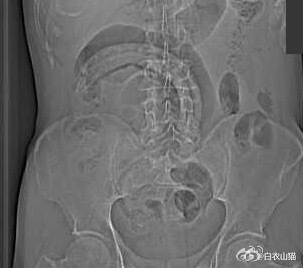

医生给他检查的时候,发现已经有腹膜炎症状,怀疑肠梗阻,拍了个片子,就是下面的片子:一条大黄鳝在肚子里。这条黄鳝还是公的黄鳝。